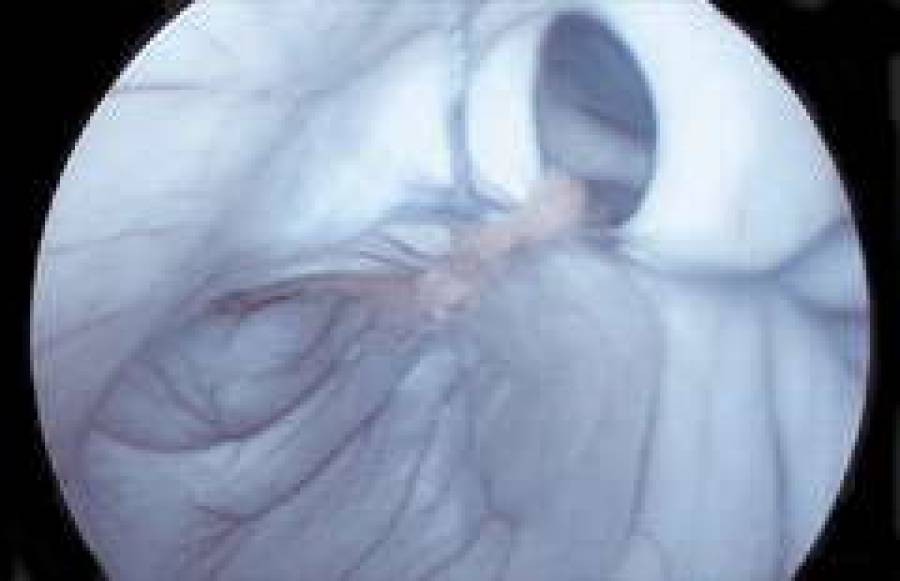

В Латвии впервые проведены операции на внутренних участках позвоночника. Благодаря эндоскопической аппаратуре нейрохирурги осуществляют практически бескровное и менее травмирующее "вторжение", освобождая зажатые нервы и корешки позвоночника.